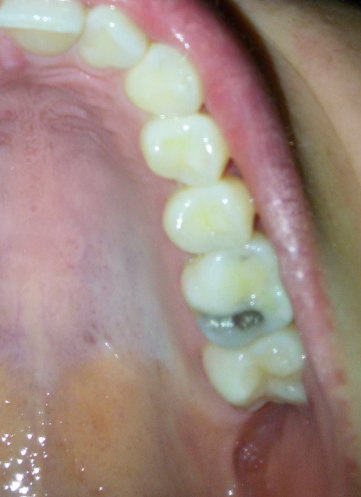

Vandaag was ik bij de tandarts en nu blijk ik een gaatje te hebben (dat was op de foto te zien en ook op de kies als een donkere vlek). Dat moet ik binnenkort laten vullen en daar is 40 minuten voor gepland. Ik schrok daarvan. Kan ik er nu van uit gaan dat het een heel groot gat is? Ik heb de foto toegevoegd, gaatje zit aan de andere kant van de vulling.